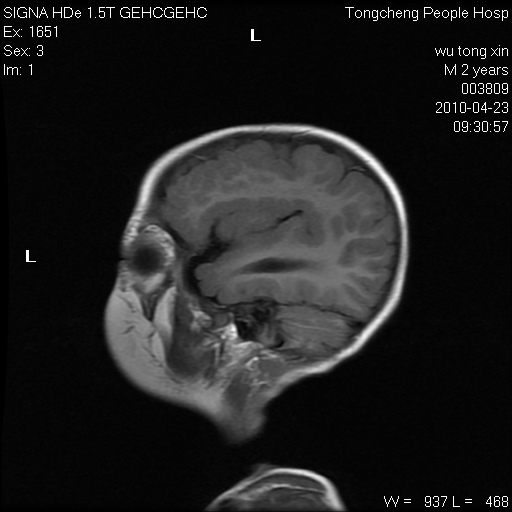

以下是引用赵物学在2010-4-25 12:43:00的发言:[br]巨脑回[br]侧脑室后角低密度影考虑hie或肾上腺脑白质营养不良?[br][br][本贴已被 赵物学 于 2010-4-25 12:51:28 修改过]

以下是引用gaoxiao在2010-4-25 16:54:00的发言:[br]巨脑回畸形。脑白质髓鞘化不良

以下是引用pujunzhi在2010-4-25 21:35:00的发言:[br]考虑 1双侧大脑皮质发育不良 2轻度脑积水 3双侧脑室后角旁片状长t1长t2信号,需继续观察,因为正常小儿此处脑白质的髓鞘化时间可以延迟到4-6岁,才显示正常。